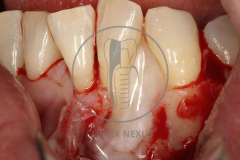

Tratamiento de defectos periodontales infraóseos en sector antero-inferior empleando gel de amelogeninas (Emdogain®) en combinación con un aloinjerto óseo (Biobank®). Paciente de 64 años, sin problemas médicos de relevancia, que presenta una periodontitis leve generalizada, pero asociada a presencia de defectos óseos verticales profundos a nivel de los espacios interdentales entre los caninos y los incisivos laterales inferiores. Tras la pertinente fase higiénica, se llevó a cabo una cirugía periodontal regenerativa, en la que, tras eliminar el cálculo subgingival (factor causal), se empleó una combinación de amelogeninas con un aloinjerto, para promover la regeneración tisular del periodonto perdido. Las imágenes clínicas y radiológicas, al año de seguimiento, reflejan un resultado terapéutico óptimo, con regeneración completa del tejido periodontal y mejora del pronóstico de los dientes involucrados.